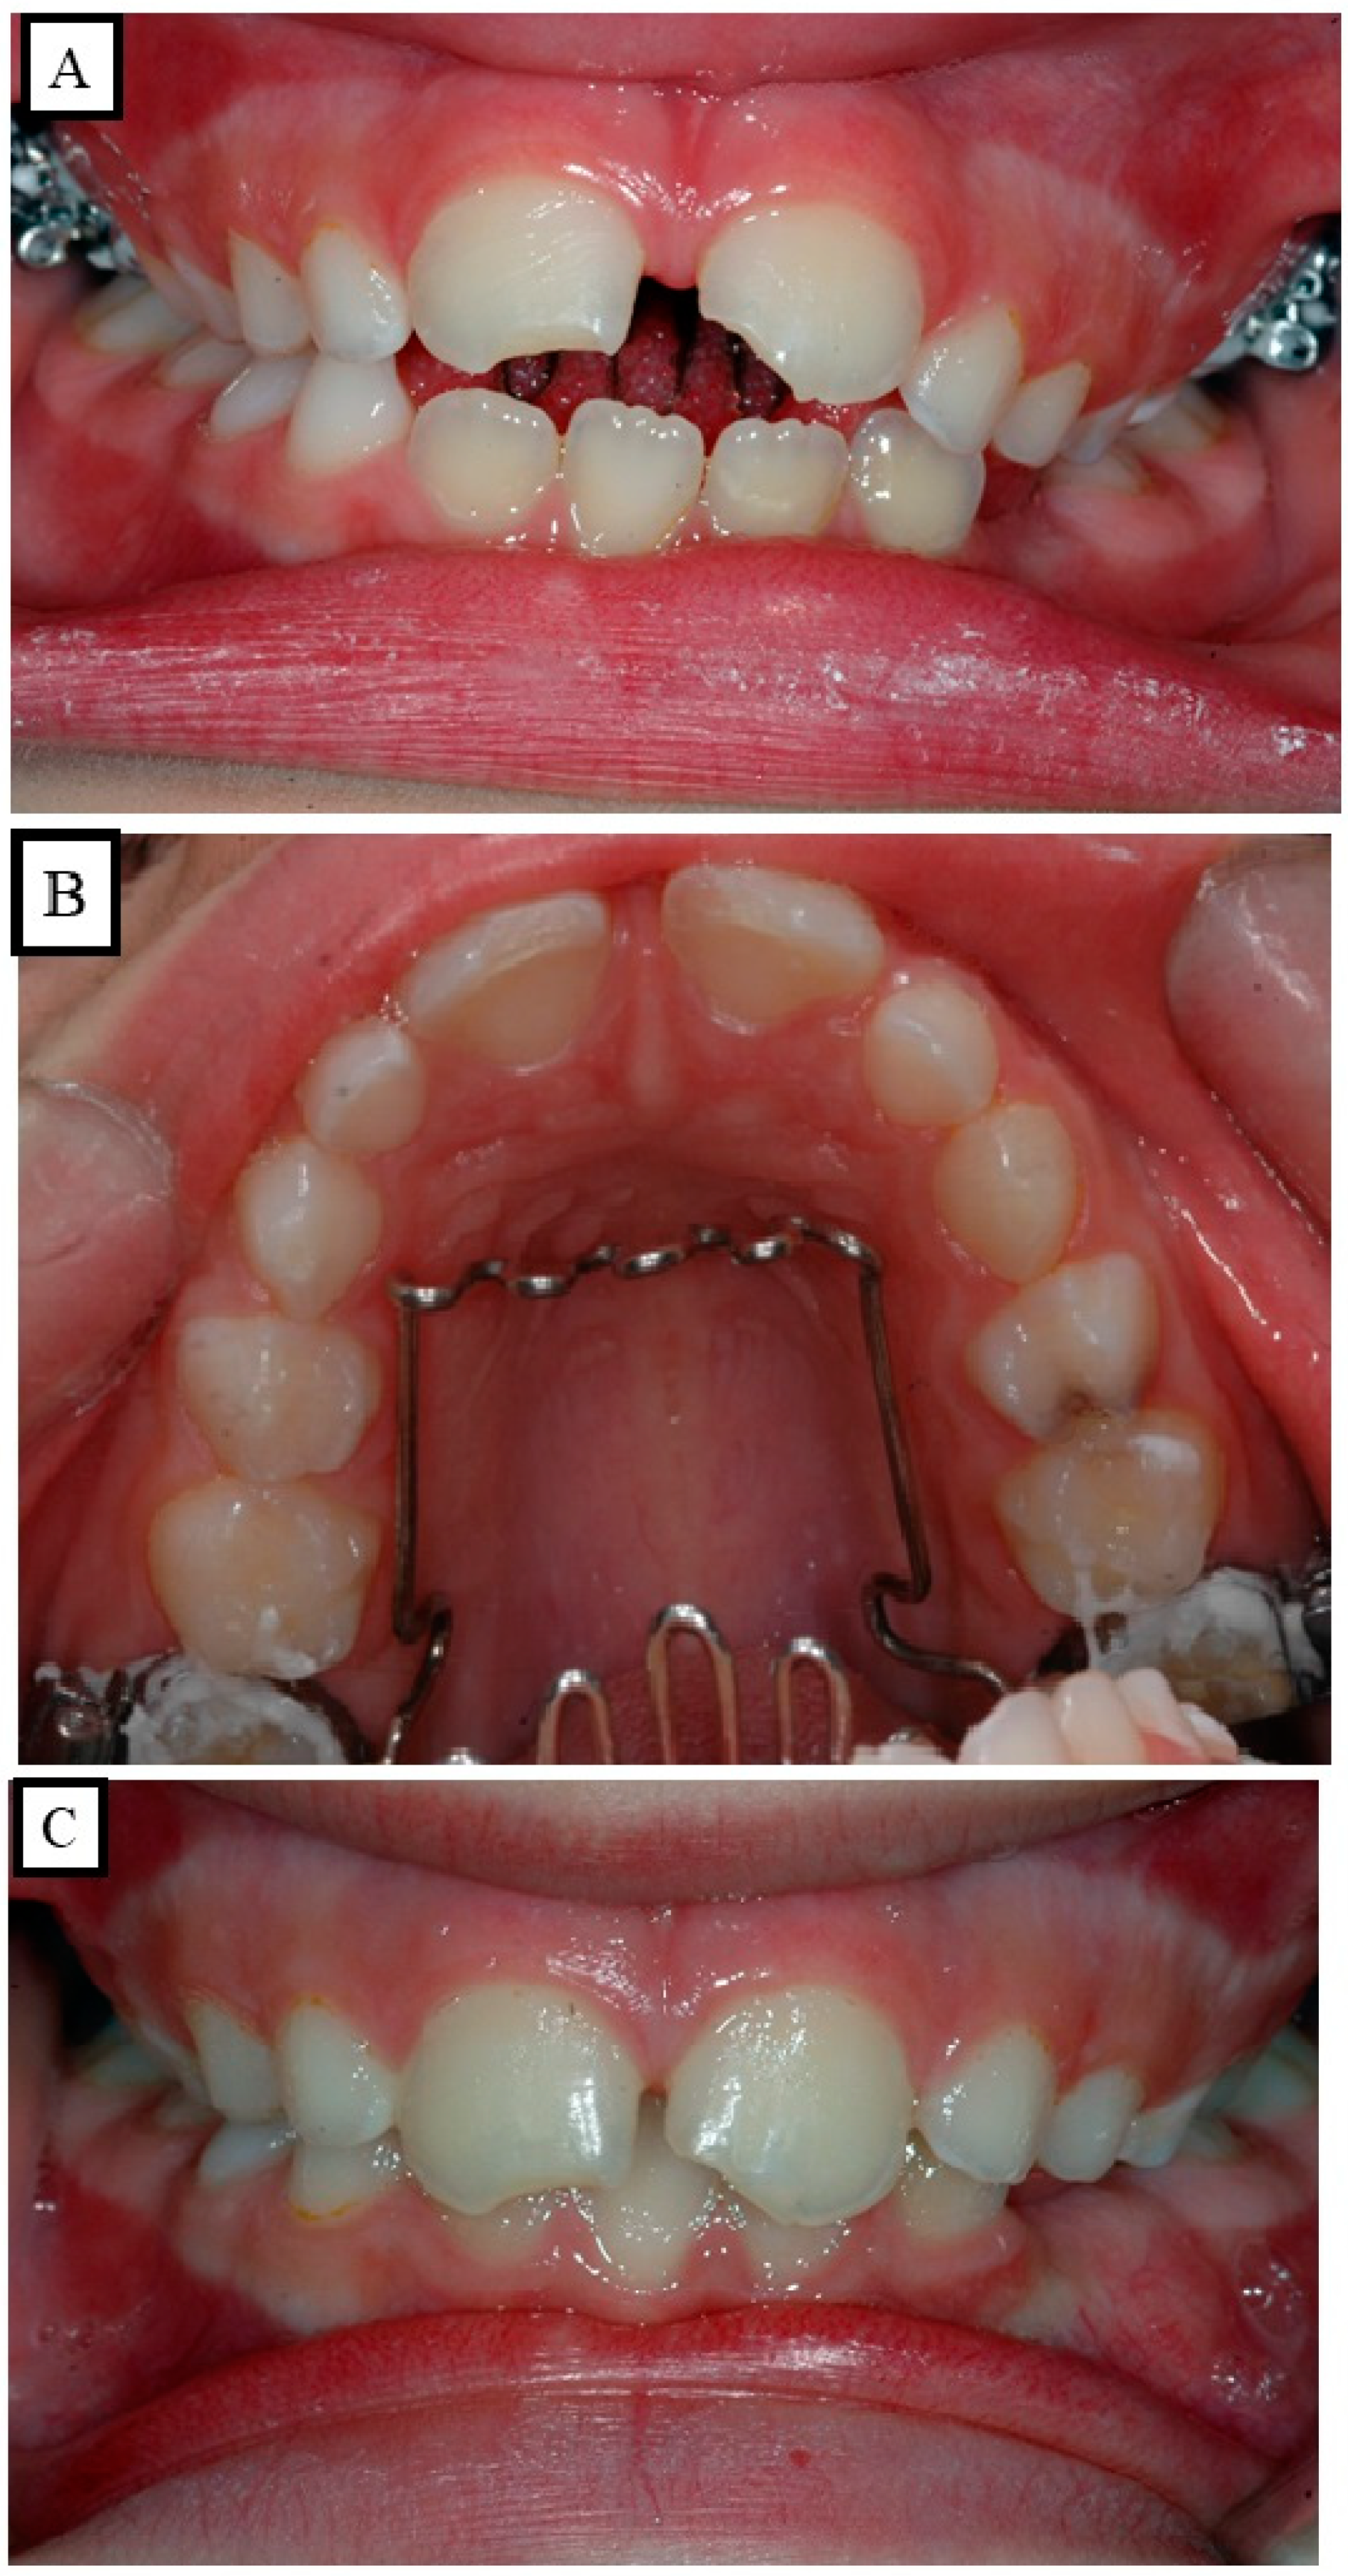

10.5. Dentoalveolar Treatment Strategy of the Dental Open Bite